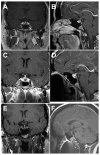

Inflammatory disease of the pituitary gland is known as hypophysitis. There are multiple histological subtypes, the most common being lymphocytic, and the pathogenesis is variable and diverse. Hypophysitis can be primary and idiopathic or autoimmune related, or secondary to local lesions, systemic disease, medications, and more. Although hypophysitis was previously accepted as an exceedingly rare diagnosis, a greater understanding of the disease process and new insights into possible etiologic sources have contributed to an increased frequency of recognition. This review provides an overview of hypophysitis, its causes, and detection strategies and management.